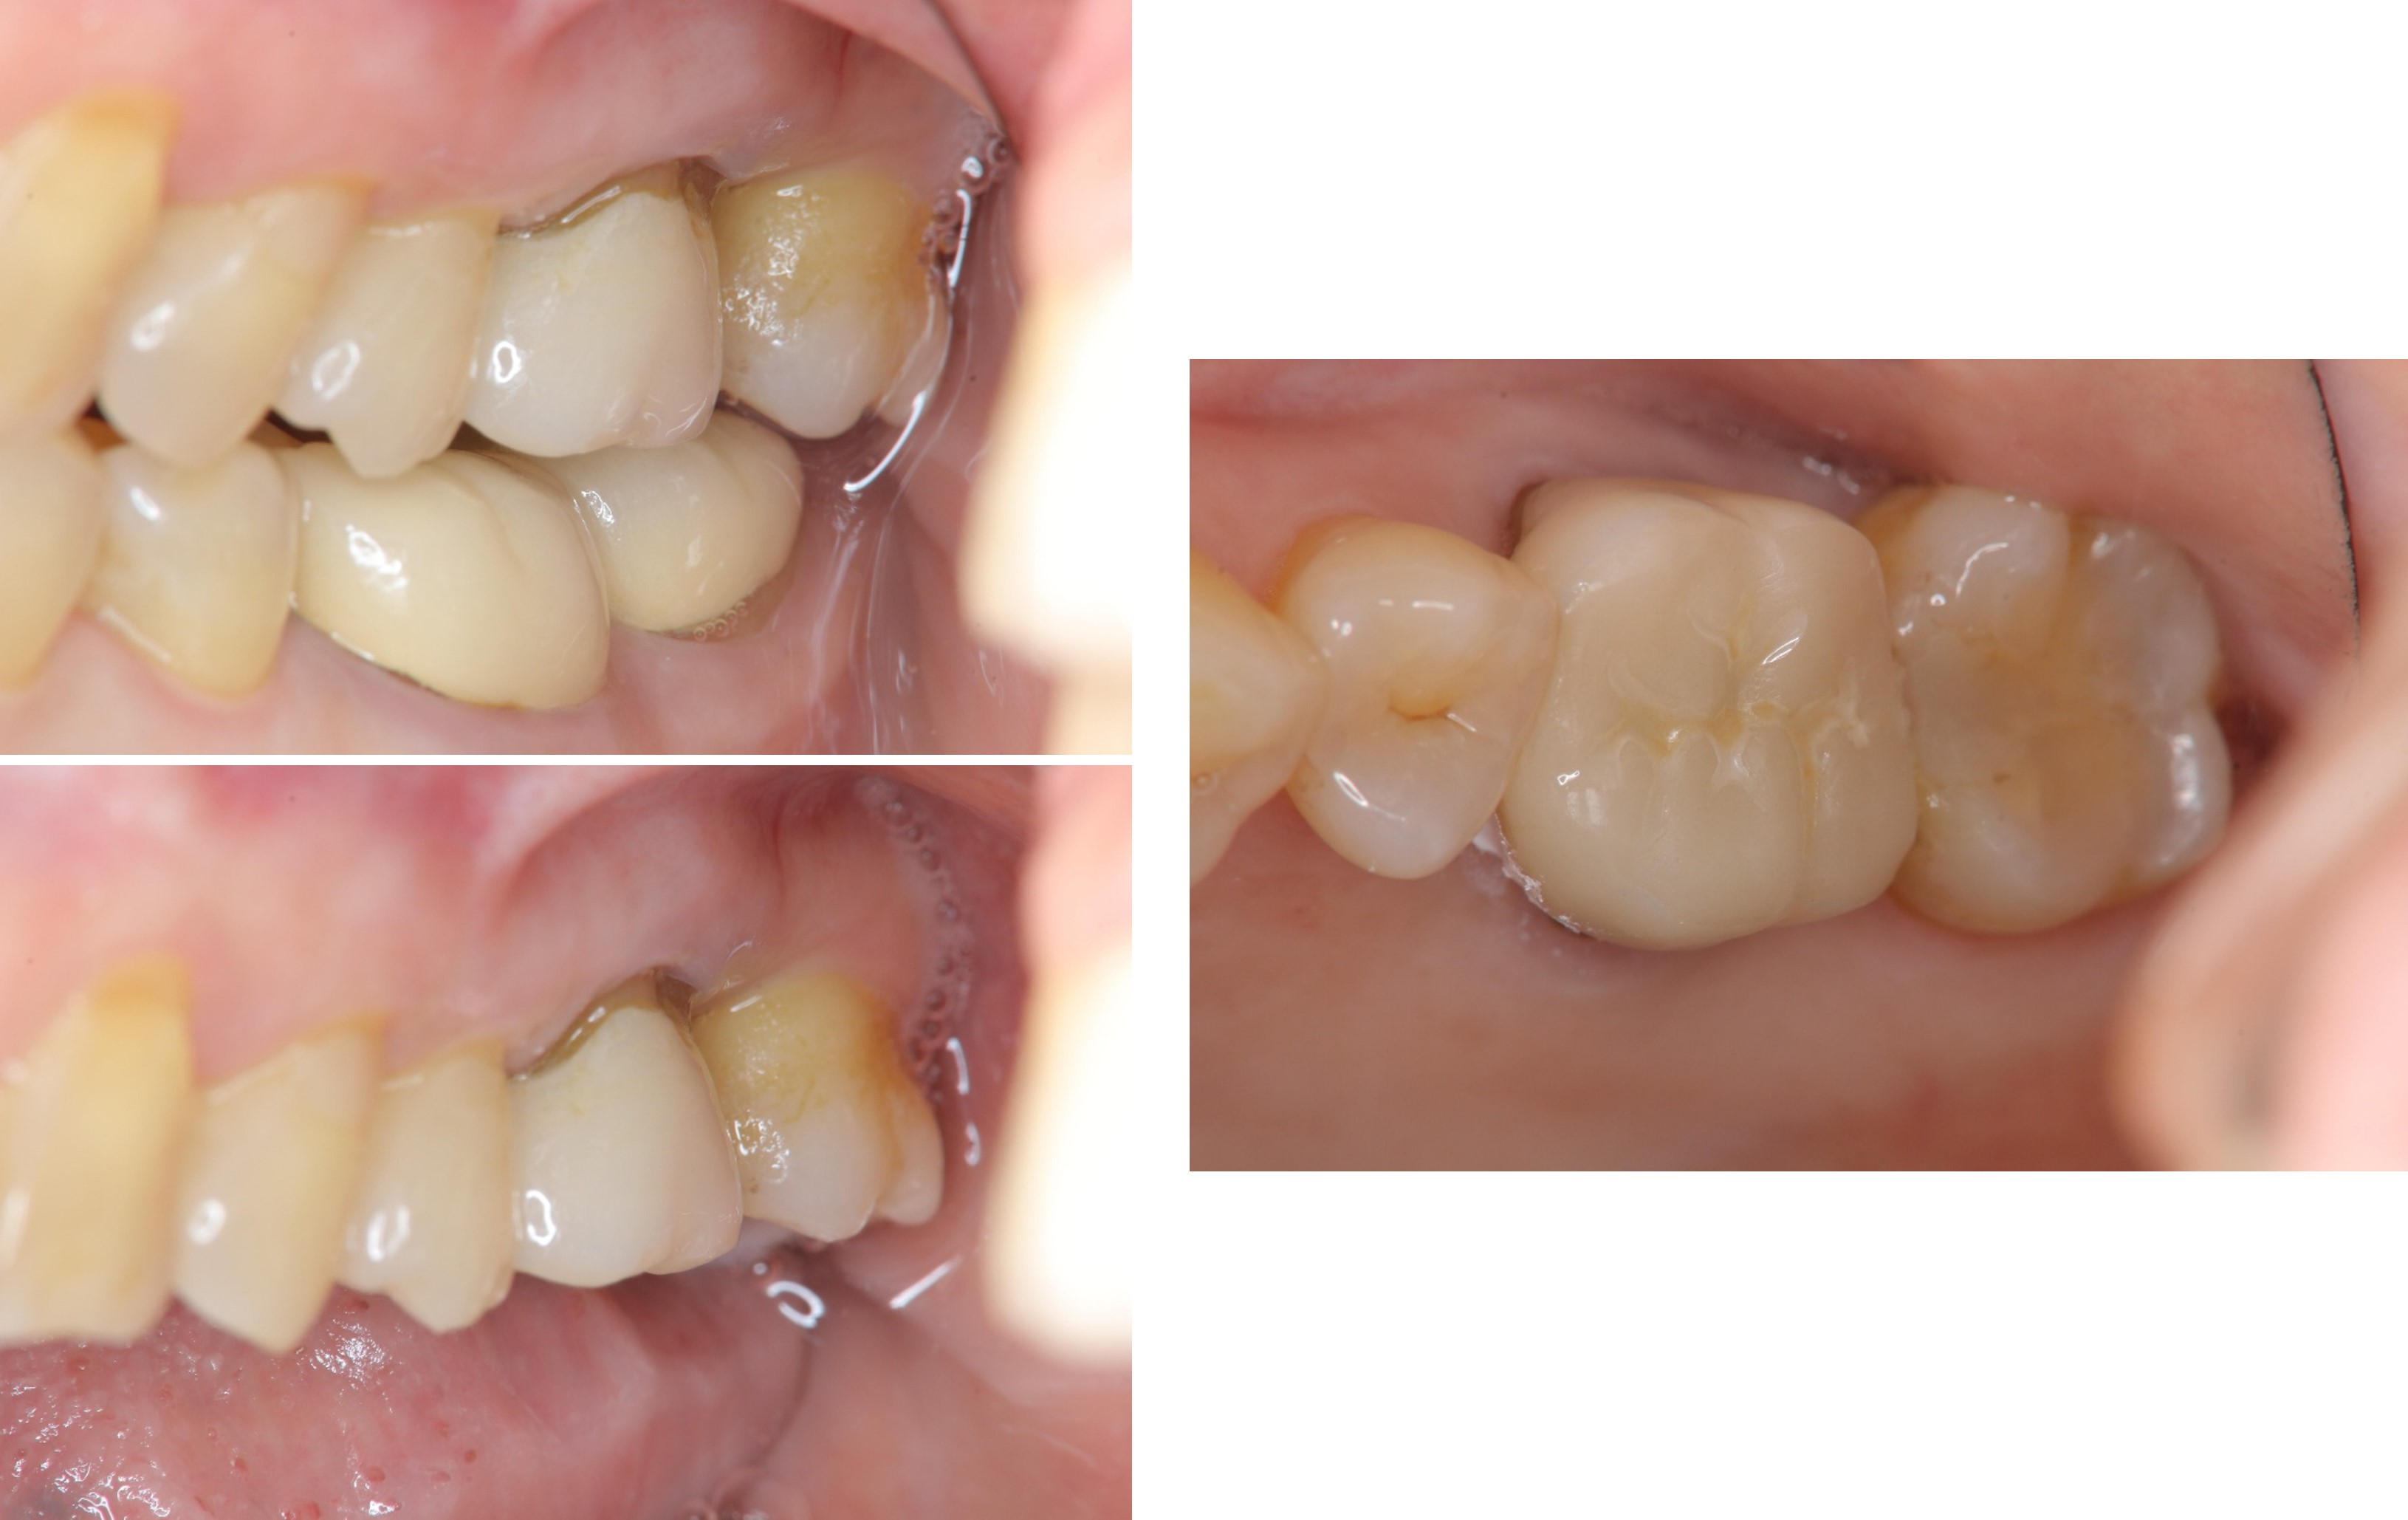

治療前,根管後大臼齒有牙裂

治療前,根管後第一大臼齒有牙裂

治療前,根管後大臼齒根部有蛀牙裂

治療後,咬合牙周適應良好

治療後,密合度良好